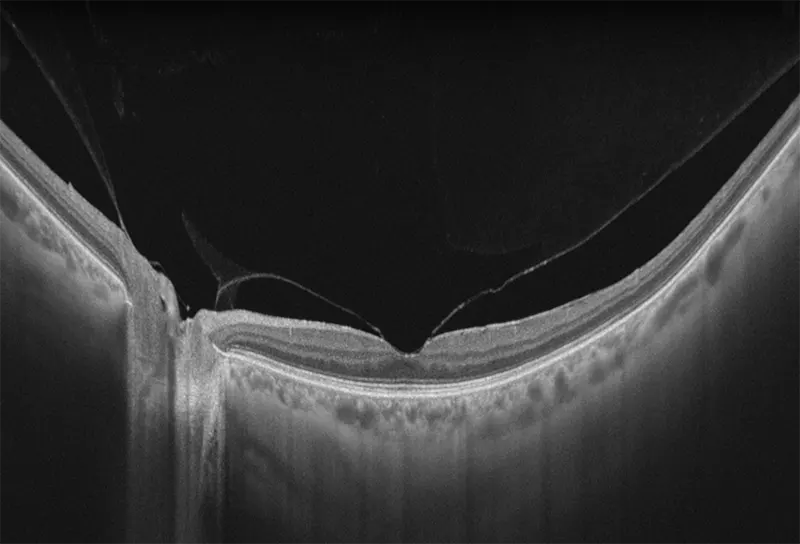

Yalkaid (YG-100K) es una nueva generación de SS-OCT con una velocidad de 100 kHz. Su principal ventaja radica en la tecnología SS de rango completo, que permite una profundidad de escaneo de 12 mm para el vítreo, la retina y la coroides, y una extraordinaria de 15 mm para el segmento anterior. La resolución óptica de <6 micrones del dispositivo garantizan una observación detallada de las estructuras anteriores y posteriores.

Con una longitud de onda de 1060 nm, Yalkaid es especialmente beneficioso para escanear pacientes con cataratas y opacidades vítreas. Su carácter invisible minimiza las distracciones por fijación. Además, sus extensos escaneos de línea de 17 mm y escaneos 3D/OCTA de 15 mm cubren un área mayor en comparación con los SD o SS-OCT tradicionales. Yalkaid está equipado con una amplia gama de herramientas de cuantificación y análisis que ayudan enormemente en la práctica clínica y la investigación. Estas características mejoran la precisión diagnóstica y contribuyen a mejores resultados para los pacientes. También tiene un Eyetracking a 60 Hz para mejorar calidad de imagen, reduciendo errores por movimientos oculares.

Galería OCTs del TowardPi Yalkaid